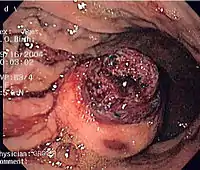

The definitive diagnosis is made with a biopsy, which can be obtained endoscopically, percutaneously with CT or ultrasound guidance or at the time of surgery. A biopsy sample will be investigated under the microscope by a pathologist physician. The pathologist examines the histopathology to identify the characteristics of GISTs (spindle cells in 70-80%, epitheloid aspect in 20-30%). Smaller tumors can usually be confined to the muscularis propria layer of the intestinal wall. Large ones grow, mainly outward, from the bowel wall until the point where they outstrip their blood supply and necrose (die) on the inside, forming a cavity that may eventually come to communicate with the bowel lumen.

When GIST is suspected—as opposed to other causes for similar tumors—the pathologist can use immunohistochemistry (specific antibodies that stain the molecule CD117 [also known as c-kit] —see below). 95% of all GISTs are CD117-positive (other possible markers include CD34, DOG-1, desmin, and vimentin). Other cells that show CD117 positivity are mast cells.

Since GISTs arise from the bowel layer called muscularis propria (which is deeper to the mucosa and submucosa from a luminal perspective), small GIST imaging usually suggest a submucosal process or a mass within the bowel wall. In barium swallow studies, these GISTs most commonly present with smooth borders forming right or obtuse angles with the nearby bowel wall, as seen with any other intramural mass. The mucosal surface is usually intact except for areas of ulceration, which are generally present in 50% of GISTs. Ulcerations fill with barium causing a bull's eye or target lesion appearance. In contrast-enhanced CT, small GISTs are seen as smooth, sharply defined intramural masses with homogeneous attenuation.